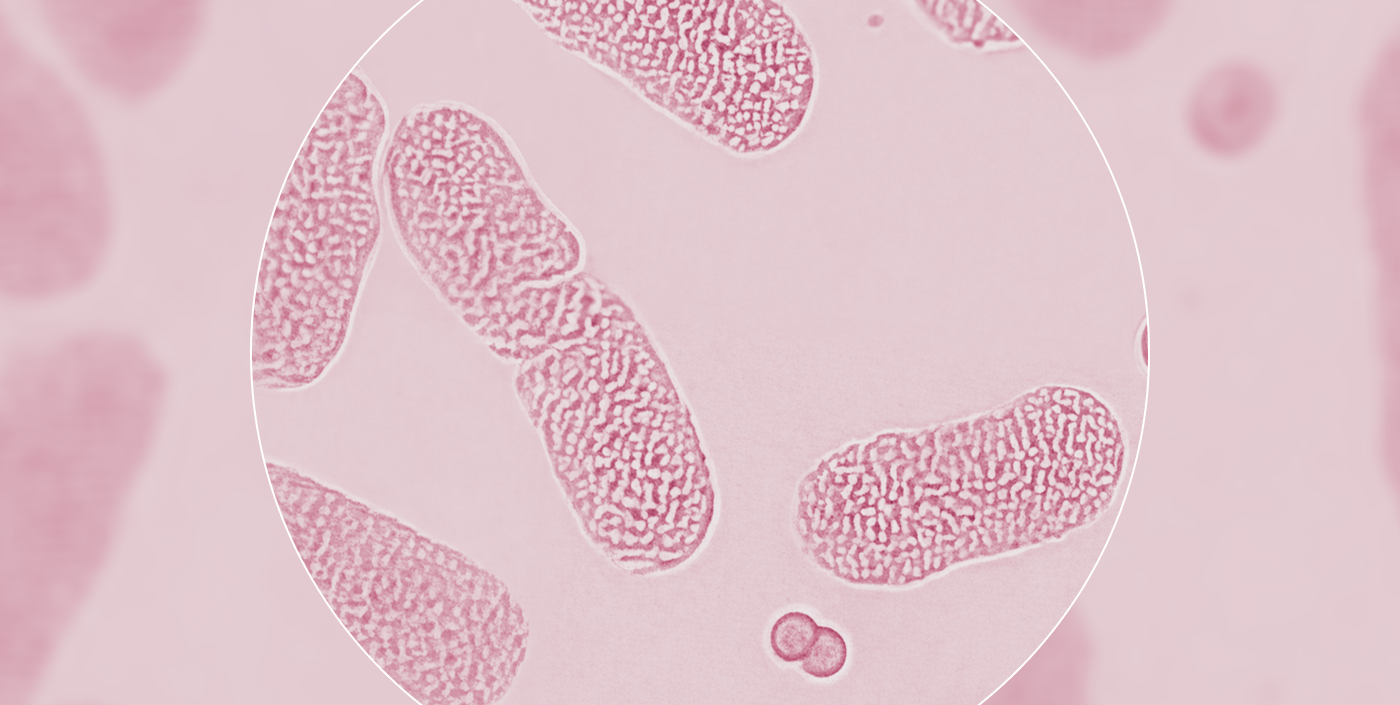

The microbiome isn’t a list of species.

It’s a living ecosystem. It should not be measured by testing fragments in isolation. The whole picture matters.

A healthy gut microbiome requires a balanced ecosystem

Like any ecosystem, a healthy gut microbiome is a balanced one. Evaluating that balance cannot be reduced to a list of well-known species. It emerges from complex microbial interactions across the whole ecosystem, from diversity to environment